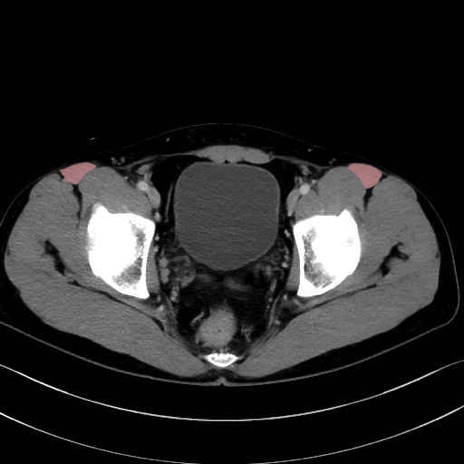

縫工筋 (Sartorius)